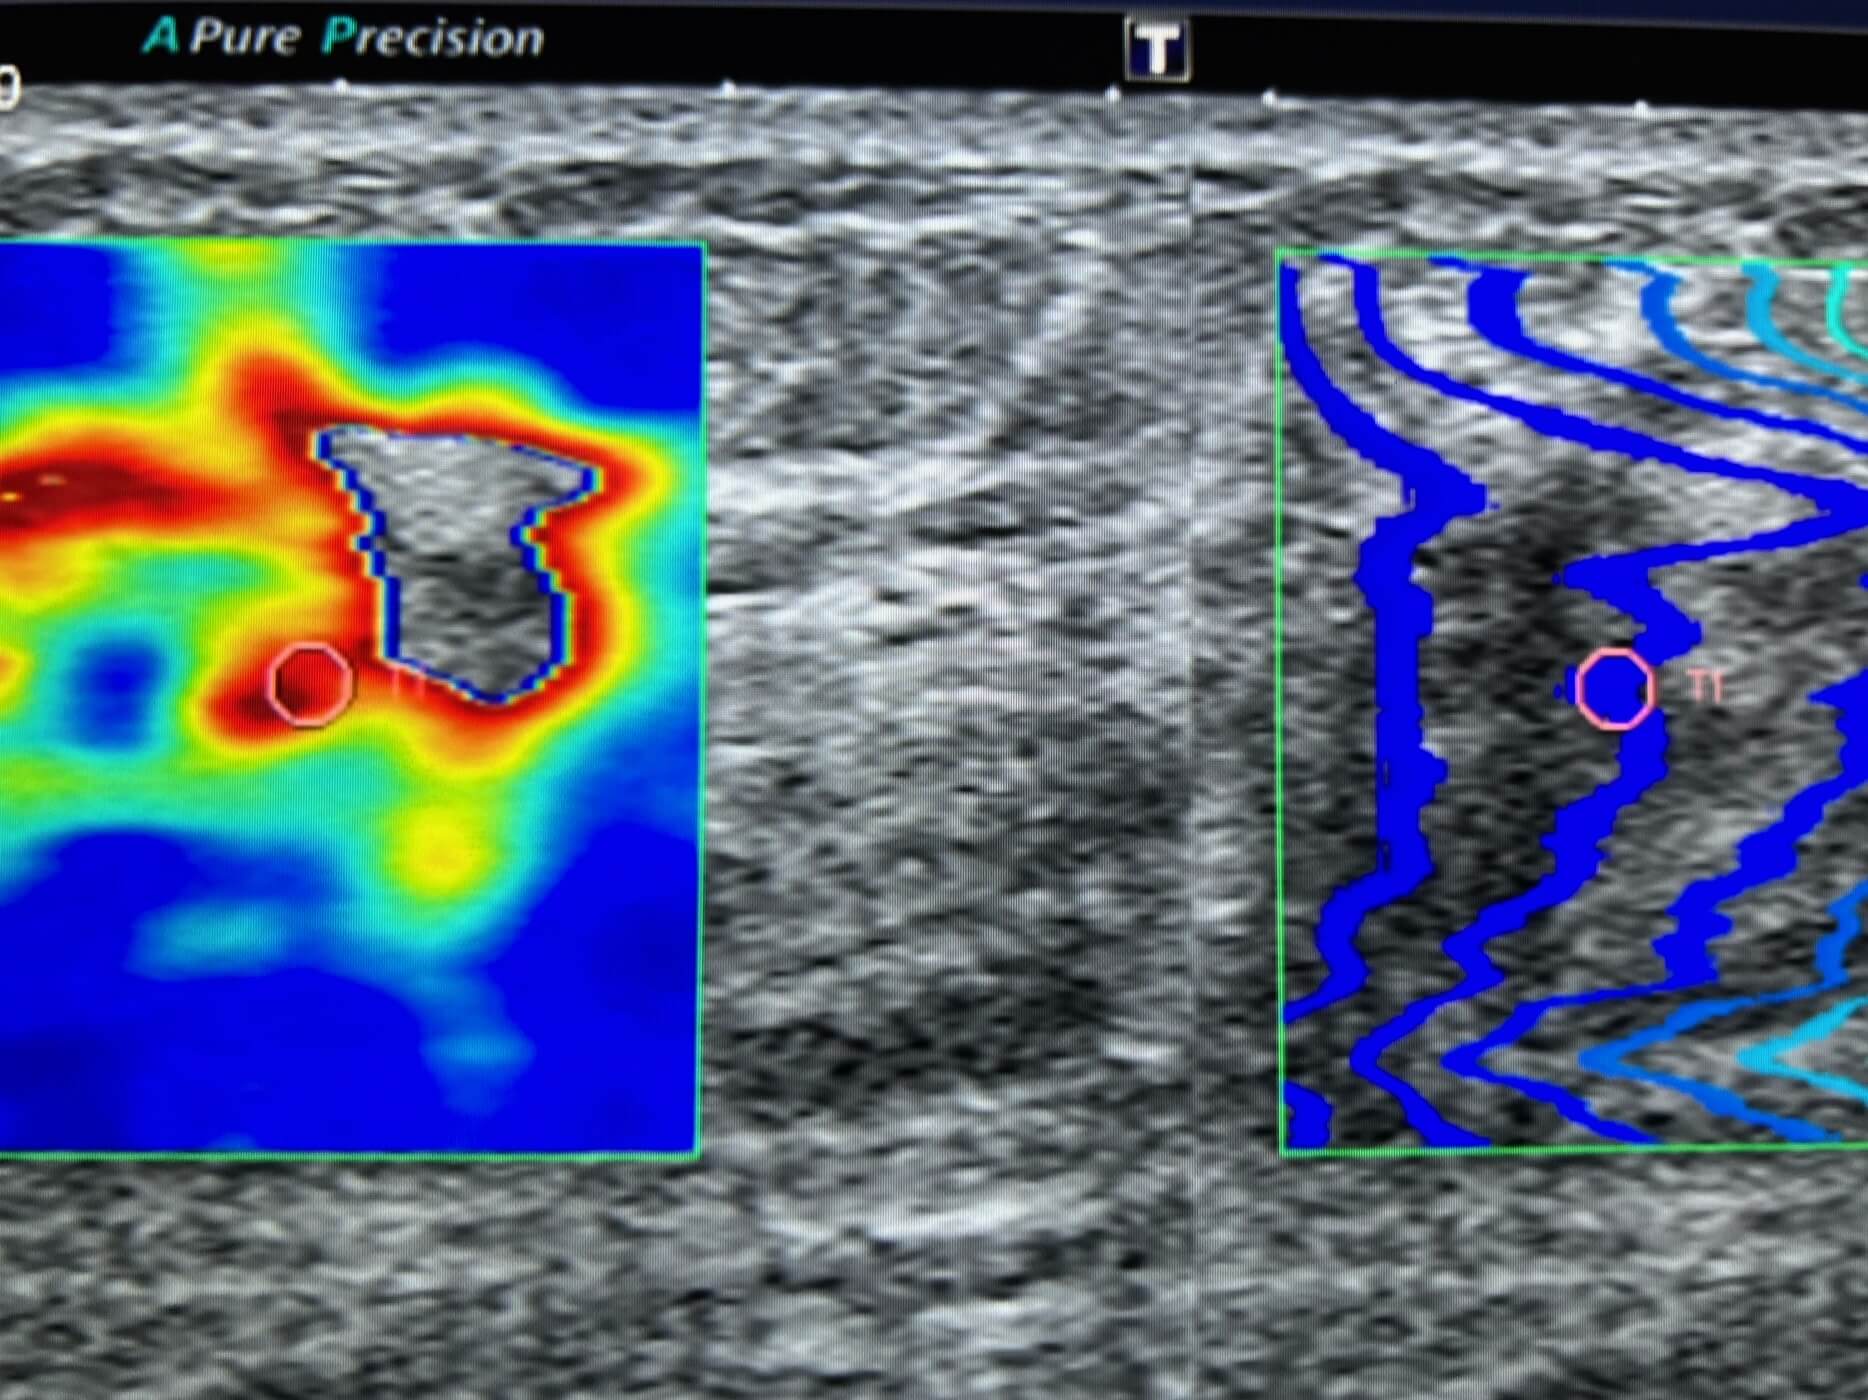

L’échographie montre une lésion hypoéchogène à contours irréguliers avec rigidité à l’étude elastographie.